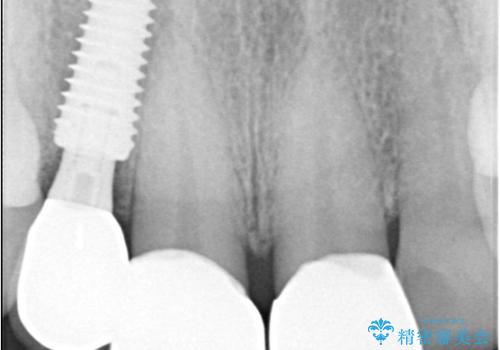

そのため今回は、右上2番を抜歯し、右上1番および左上1番をオールセラミッククラウンで審美的に修復しました。

インプラント治療は、低侵襲で短期間に行える「抜歯即時インプラント治療」を選択しました。

この方法は、抜歯したその日にインプラントを埋入し、手術が1回で済むのが大きな特徴です。

治療期間も短く、抜歯からわずか3か月でオールセラミッククラウンを装着することができます。